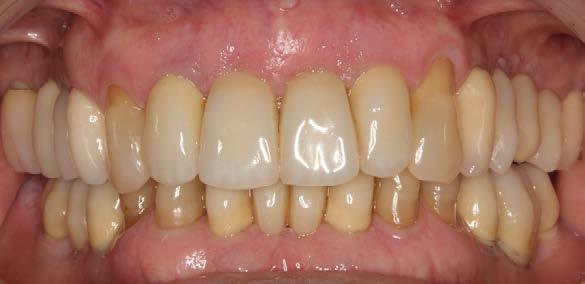

La paciente continúa en seguimiento. A los 8 años, la estabilidad de los tejidos duros y blandos, así como la estética de la rehabilitación, era completa (Figura 9-11). A los 12 años se observó

una buena progresión del tratamiento, sin cambios reseñables (Figura 1214). A los 20 años de seguimiento se constató una evolución estable, sin pérdida ósea en dientes ni implantes, y con buena salud de los tejidos periimplantarios (Figura 15-17).

Figuras 9-10. Imágenes de seguimiento clínico a los 8 años.

Figuras 12-13. Imágenes que muestran el mantenimiento de los tejidos blandos y la estética a los 12 años.

no solo clínicas, sino también sensoriales y psicológicas.16,17,31,32 La propiocepción que brindan los dientes remanentes mejora la distribución de fuerzas y facilita el control funcional. Esta ventaja se potencia cuando los dientes preservados forman parte de guías funcionales clave, como los caninos.33,34

Además, los dientes unirradiculares suelen presentar una mejor respuesta al tratamiento periodontal en casos de EP avanzada, ya que su anatomía es más accesible para el control mecánico y presentan menor afectación en furcaciones.35,36 Como se evidenció en este caso, el compromiso del paciente, junto con un seguimiento clínico riguroso y personalizado, fue determinante para lograr estabilidad a largo plazo. 37

Figuras 15-16. Imágenes intraorales a los 20 años de seguimiento.

Figura 17. Radiografía final que evidencia la estabilidad completa de los tratamientos a los 20 años.